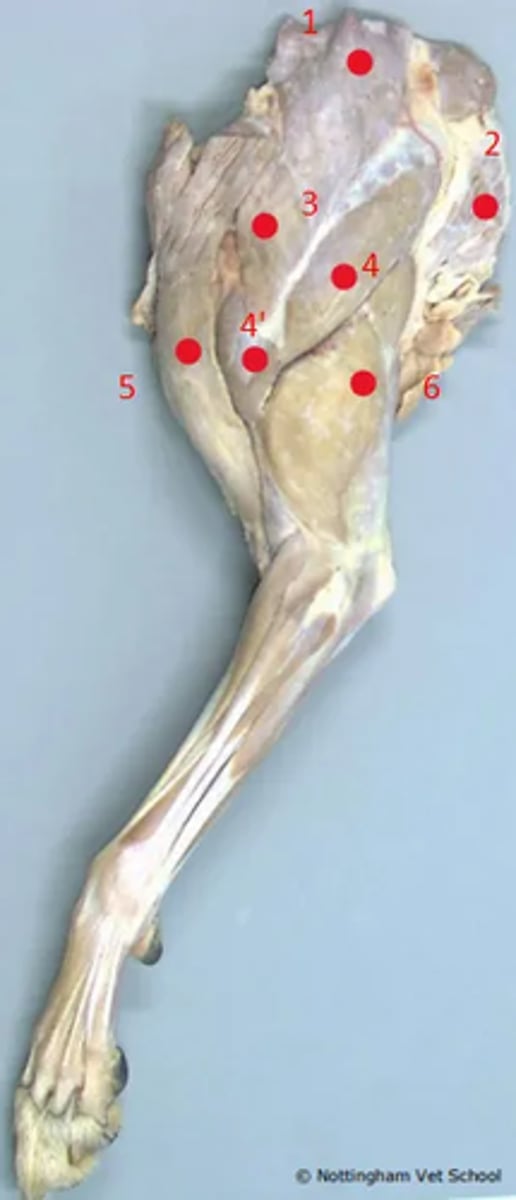

Identify the structures highlighted in the proximal forelimb

1. Trapezius

2. Latissimus dorsi

3. Omotransversarius

4. Scapula part of deltoid

4'. Acromial part of deltoid

5. Brachicephalicus (cleidocephalicus)

6. Triceps brachii